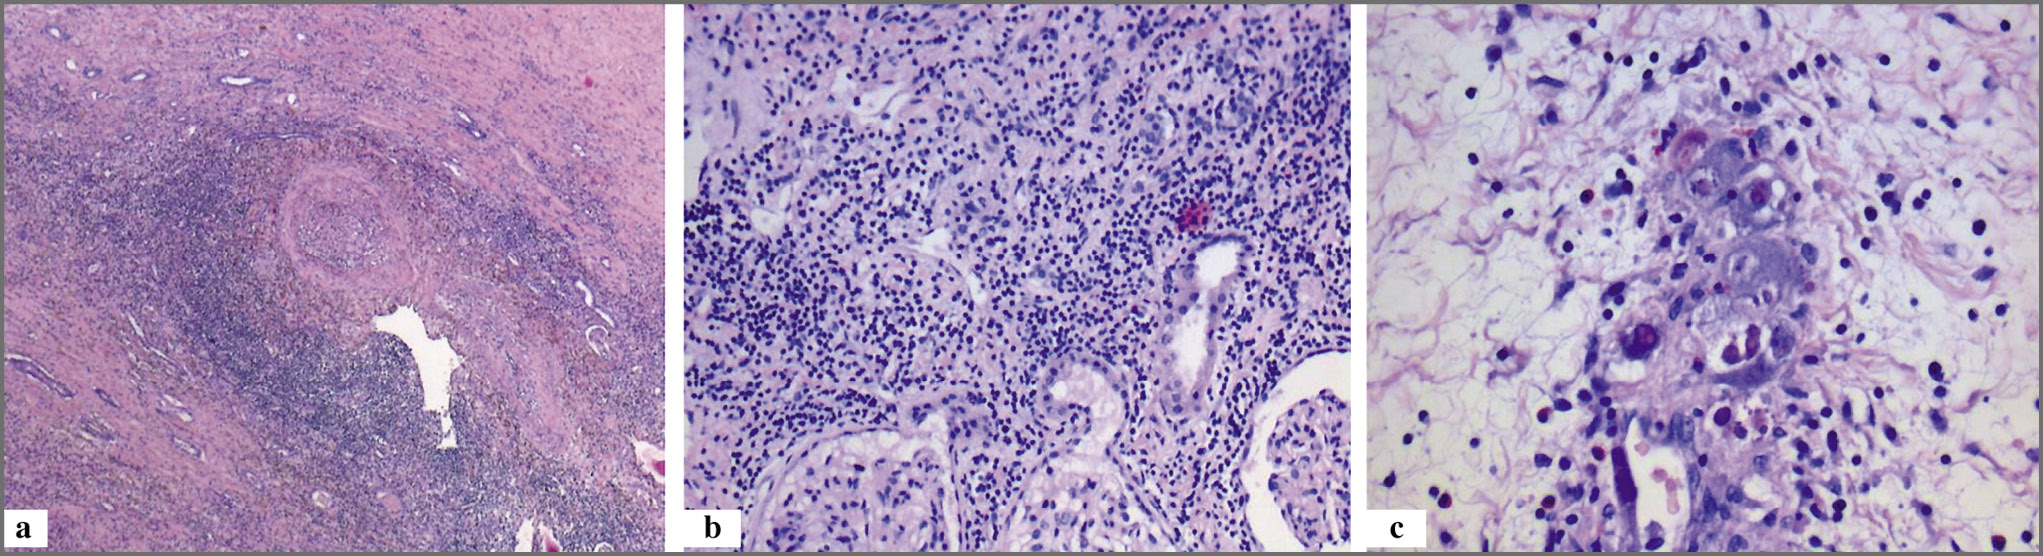

Пациентка С., 26 лет, диагноз: хронический гломерулонефрит, ХБПС5. На программном гемодиализе с 2015 г. В 2016 г. выполнена трансплантация аллогенной трупной почки. На 4-е сутки после ТАП на фоне индукционной иммуносупрессивной терапии отмечено уменьшение темпа диуреза. Уровень креатинина составлял 527 мкмоль/л, мочевина – 31,4 ммоль/л. По данным ультразвукового исследования отмечено повышение индекса резистентности артерий почечного трансплантата, IR=1. При гистологическом исследовании биоптата трансплантата обнаружена картина острого гуморального отторжения (рис. 1).

Рис. 1: a – крупный участок некроза. На границе с некротизированной тканью присутствует артерия крупного калибра инфильтрацией стенки лимфоидными клетками, значительным сужением просвета за счет пролиферации эндотелия. Выражена периваскулярная лимфоидная инфильтрация с примесью единичных гранулоцитов, окраска гематоксин-эозином, ×50; b – в ткани почки лимфоидная инфильтрация носит очаговый, периваскулярный характер, присутствуют мелкие фокусы тубулита, окраска гематоксин-эозином, ×200; c – артериола с наличием в стенке гигантских клеток с эозинофильными внутриядерными включениями (косвенные признаки активной ЦМВ-инфекции), окраска гематоксин-эозином, ×400.